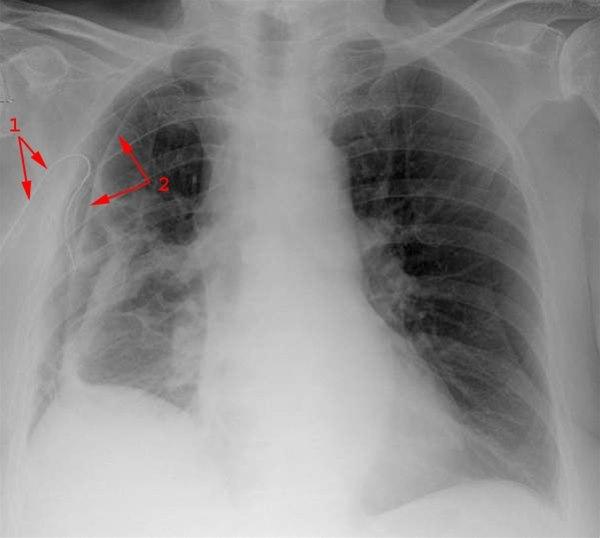

Pneumothorax med luftkappe på høyre side

Mellomgolvet er løftet

Drenasje til pleurahulen (1)

Overflaten av den delvis sammenklappede lungen (2)